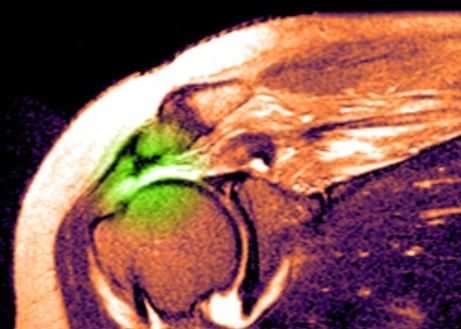

МРТ плечевого сустава. Т2-взвешенная корональная МРТ. Разрыв вращательной манжеты. Цветовая обработка изображения.

Разрыв вращательной манжеты – также характерное повреждение области плеча – может быть связан как с травмой, так и дегенеративными процессами. Разрывы вращательной манжеты бывают полные и неполные. Кроме того, по МРТ плечевого сустава выделяют 3 градации, в основе которых лежит не только изменение сигнала на Т2-зависимых томограммах, но и морфологические изменения сухожилия.

МРТ. Корональная Т2-зависимая томограмма с подавлением сигнала от жира. Полный разрыв сухожилия надостной мышцы.

При МРТ плечевого сустава косвенным признаком разрыва вращательной манжеты служит высокий сигнал на Т2-взвешенных от поверхности сустава до субакромиальной (субдельтовидной) сумки. Частичные разрывы чаще всего по передней поверхности сухожилия м.supraspinatus, реже примыкая к большой бугристости или сухожилия м. infraspinatus.